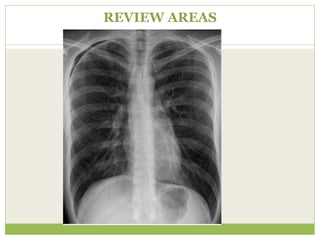

Key points - Review areas

๏‚— Apices - Pneumothorax?

๏‚— Bones/soft-tissues - Fractures/density?

๏‚— Cardiac shadow- Consolidation/mass?

๏‚— Diaphragm - Pneumoperitoneum?

๏‚— Edge of the image - Unexpected findings?

๏‚— Mnemonic - ABCDE

REVIEW AREAS